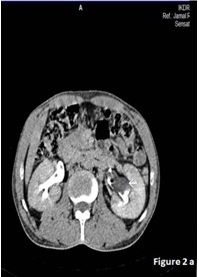

Another 40-year-old non diabetic male patient presented with flank pain and haematuria. Physical and Laboratory Findings were within normal limits. Renal function tests were normal. Plain X ray KUB was normal. On Ultrasound, presence of bilateral hydronephrosis with internal echoes was seen. Retrograde Pyelography showed multiple filling defects. CT IVP showed presence of hydronephrosis with multiple non enhancing filling defects in Pelvi calyceal system which also extended in to pelvis [Table/Fig-2a,b]. Cupping of all the calyces was seen consistent with the Egg in the Cup deformity seen typically in renal papillary necrosis. So, radiologically diagnosis of RPN was made and he was maintained conservatively and is asymptomatic on follow up.

Axial section of Delayed phase of CT scan showing normal excretion of contrast with multiple filling defects in Pelvi calyceal system and pelvis (white arrow).